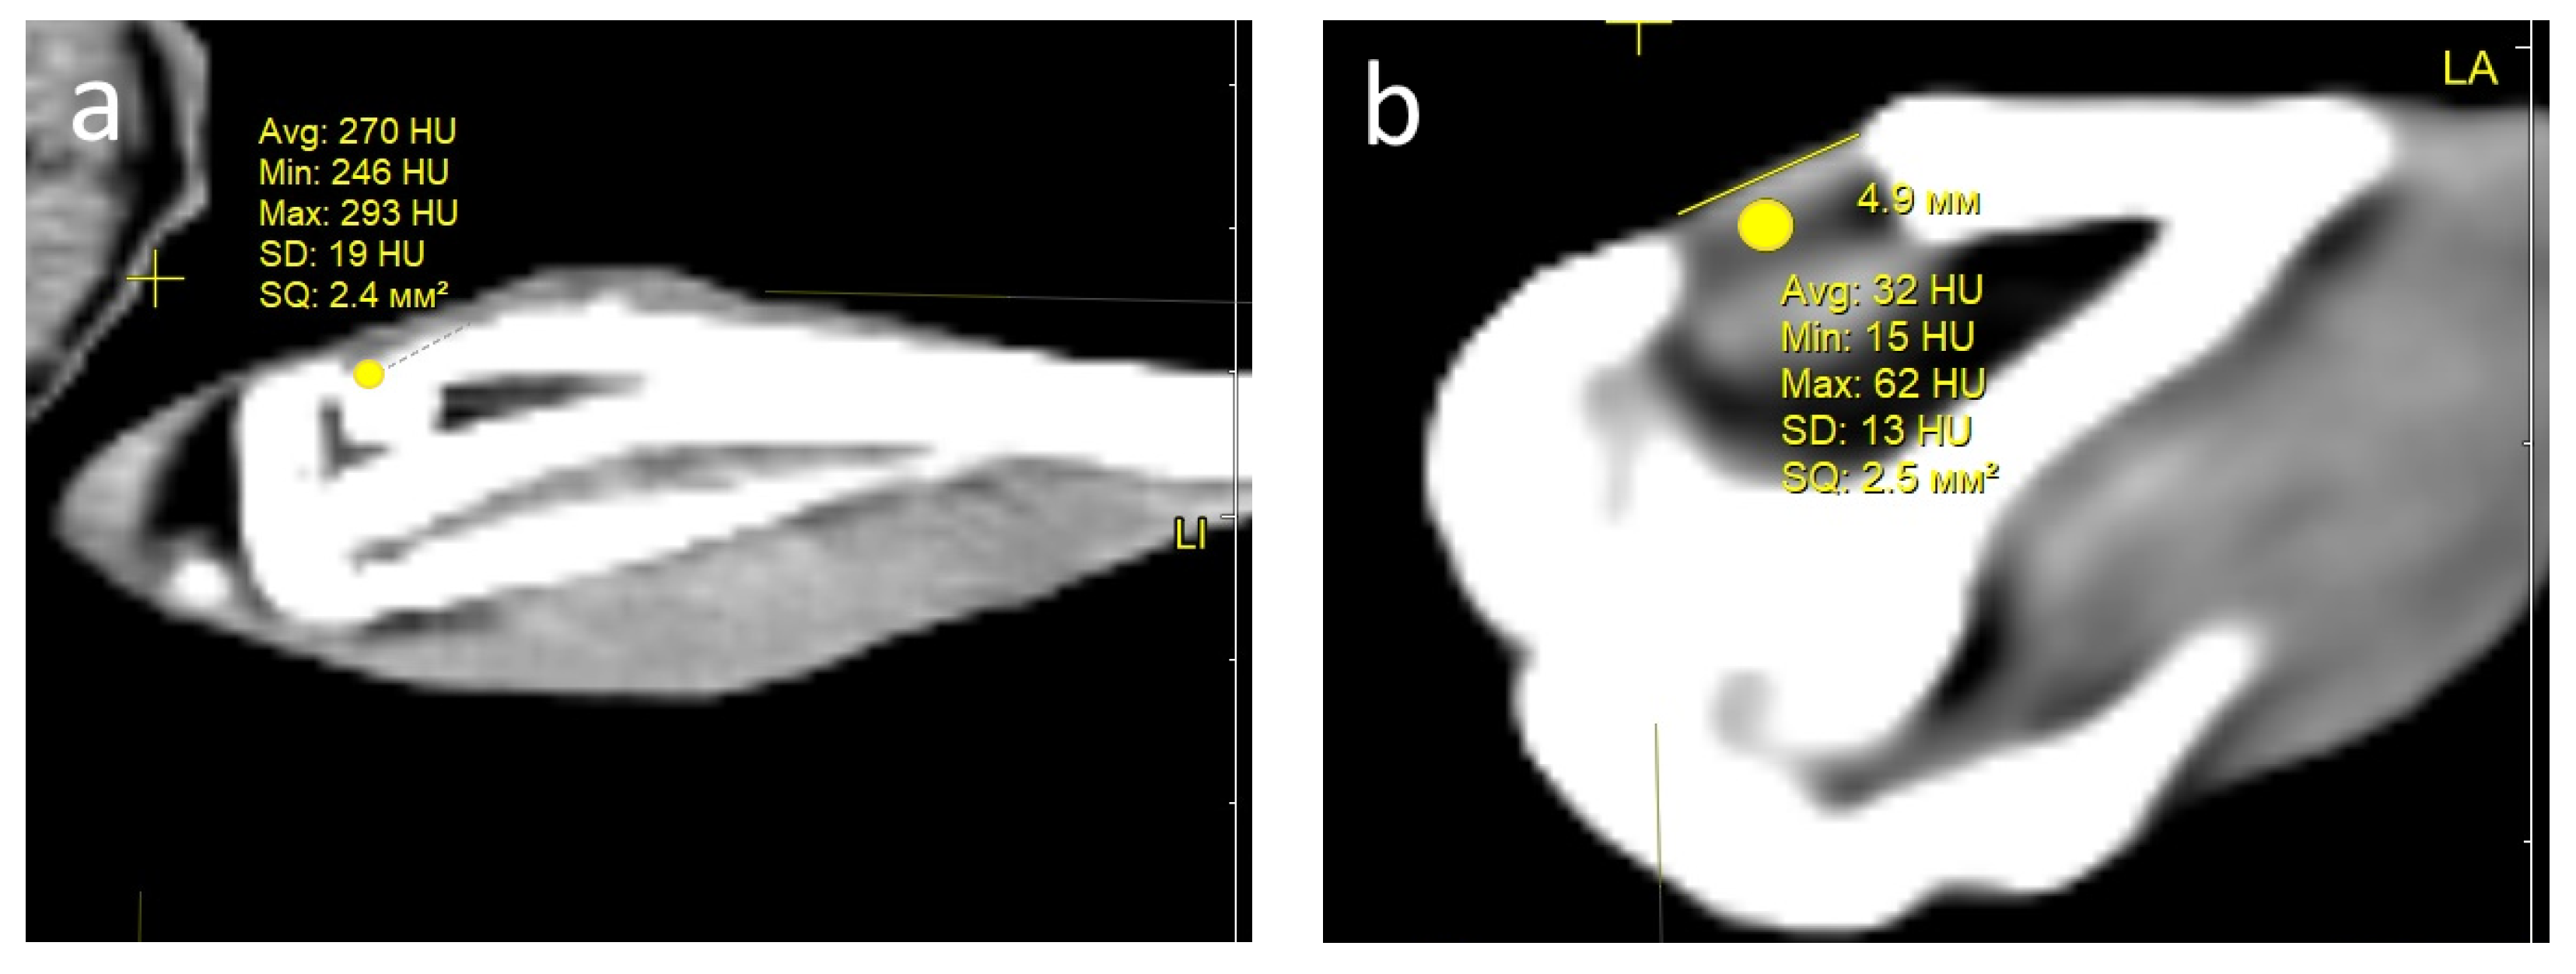

Condition of the defect area and computed tomography (CT) examination. One month after the operation, all rabbits in both groups showed signs of regeneration of the inflicted experimental bone defect in the form of a decrease in its size by 1–2 mm. The size of the defect, determined by CT measurements on the day of surgery, corresponded to the intraoperative measurements. At the CT densitometry assessment of the area after 1 month, the Hounsfield index among all rabbits in the control group (grafted osteoplastic matrix) was 69–271 HU. The average values of the X-ray density of the entire volume of the graft in the animals in this group were 142–229 HU, which indicated the heterogeneous nature of the cavity contents (Figure 8a). The values of this parameter in the experimental group (hybrid polymer) ranged from 15–89 HU. The average values of the X-ray density of the entire volume of the graft in the animals in this group were 31–67 HU (Figure 8b). This very insignificant scattering of values indicated the homogeneity of the graft. In the cortical bone structures adjacent to the defect, the Hounsfield index value was 680–720 HU.

Figure 8.

CT scan—section through the center of the implant in the sagittal direction, observed: at 1 month: (a) control, (b) experiment; at 2 months: (c) control, (d) experiment; at 6 months: (e) control; (f) experiment.

In the animals removed after 2 months, a further decrease in the size of the defect was seen, decreasing to an insignificant size of 1–2 mm. All animals in the control group (grafted osteoplastic matrix) had absolute values of the Hounsfield index from 10–457 HU. The average values of the X-ray density of the entire volume of the graft in the animals in this group were 171–231 HU (Figure 8c). The minimum value in the experimental group (hybrid polymer) was 96 HU, the maximum was 643 H. The average values ranged from 195–453 HU (Figure 8d). The measurements did not reveal any pathological changes in the cortical bone structures adjacent to the defects.

After 6 months, complete recovery of the applied defect was demonstrated in all animals in both groups. However, the Hounsfield index in the control group (grafted osteoplastic matrix) ranged from −60 to 910 HU and continued to demonstrate the heterogeneity of the graft tissue, along with occasional increases above the usual values for shin bone. The average values ranged from 305–577 HU (Figure 8e). The values of the X-ray density of the central part of the graft in the experimental group (hybrid polymer) ranged from 204–814 HU. The average values ranged from 426–615 HU (Figure 8f).

The dynamics of the changes in X-ray density in the defect area are shown in Table 2.

Table 2.

Hounsfield index values (in HU).

Therefore, the CT data, which includes CT densitometry of the central area of the graft, indicate that the processes of reparative regeneration in the animals in the control and experimental groups differed to some extent. In the control group, at all assessment points, the density of the graft was convincingly heterogeneous, and included areas where minimal X-ray shadow intensity persisted for 6 months. The graft placed into the bone defect in the rabbits in the experimental group demonstrated a stable increase in X-ray density, together with a less significant scatter between the minimum and maximum values of the X-ray shadow intensity.

Consequently, based on the CT image analysis, the authors determined the development of a more uniform structure; therefore, it was concluded that there were more active regenerative processes in the bone defects of the rabbits in the experimental group.